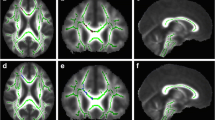

Differences in FA regions between the two groups occurred mainly in the left cerebrum, WM and GM of the frontal and temporal lobes, the rectus, the frontal superior inferior orbital area, the caudate, the frontal gyrus, and the subcallosal gyrus. These differences can be seen in Table 2 and in Fig. 1a–c.

Differences in MD regions between the two groups occurred primarily in the cerebrum bilaterally, WM and GM of the limbic lobes, the uncus, the left frontal lobe, the rectus, the right temporal lobe, the parahippocampal area, and the rectus. These differences can be seen in Table 3 and in Fig. 2a–c.

Differences in MK regions between the two groups occurred mainly in both cerebral hemispheres, and several WM and GM regions of the frontal and parietal lobes. These differences can be seen in Table 4 and in Fig. 3a–c.